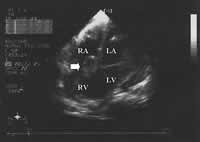

图2 UCG示右房、右室间肿块(↑)提示肿瘤心腔内转移。RA=右房,RV=右室,LA=左房,LV=左室

实验室检查 血常规 白细胞11.4×109/L,中性粒细胞89.3%,血红蛋白131 g/L,血小板314×109/L;尿常规、便常规+潜血正常。丙氨酸转氨酶(ALT)497 U/L,天冬氨酸转氨酶(AST)532 U/L,碱性磷酸酶(ALP)186 U/L,谷氨酰转肽酶(GGT)136 U/L,总胆红素(TBik)1.63 mg/dk(正常值1.3 mg/dk),直接胆红素(DBik)0.80 mg/dk,白蛋白(ALB)33 g/L,白蛋白/球蛋白(A/G)1.0,乳酸脱氢酶(LDH)866 U/L,血清肌酐、尿素氮正常;凝血酶原时间18.1 s,激活的部分凝血活酶时间27.2 s;乙肝表面抗原(HBsAg)、抗HIV抗体(-)。B超:胰腺体部5.7 cm×4.3 cm低回声占位,回声欠均匀;肝脏回声均匀,胆管无扩张;腹水。CT(图1):双侧胸腔积液,下肺实变;胰体部软组织肿块,胰腺癌可能大,腹水,无腹膜后淋巴结肿大。心电图(ECG):房室交界性心律,短阵房性心动过速,伴室性期前收缩,呈二联律。超声心动图(UCG):下腔静脉(IVC)明显增宽(内径29 mm),其内可见实质占位回声,右房(RA)、右室(RV)及RV流出道内分别见61 mm×22 mm、32 mm×21 mm、30 mm×23 mm不均质的实质肿块(其中RA内充满占位),考虑肿瘤回声;左室收缩功能(射血分数54%)及室壁运动未见异常,左房轻度增大(内径41 mm),轻度肺动脉高压(收缩压46 mmHg),少量心包积液(图2、3)。考虑胰腺肿瘤(胰腺癌可能性大)心脏转移诊断基本成立。本应进一步查CA199以支持胰腺癌诊断,行胸腹部增强CT、头颅CT、核素骨扫描除外其他部位转移的可能,为手术做准备。但因患者病情危重(随时有RV流出道梗阻加重、猝死可能),手术风险极大,且家庭经济困难,家属表示放弃进一步治疗离院。